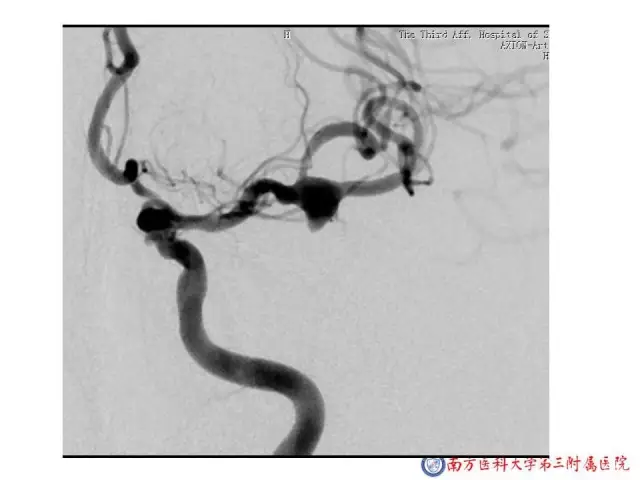

今天为大家分享的是“强生医疗CNV-神经介入专栏”第二十五期,由南方医科大学第三附属医院神经外科主任黄理金教授带来的“Enterprise支架辅助栓塞动脉瘤的优势”精彩讲课视频及PPT,欢迎观看。文章仅代表作者个人观点,如有不同见解,欢迎同道斧正!